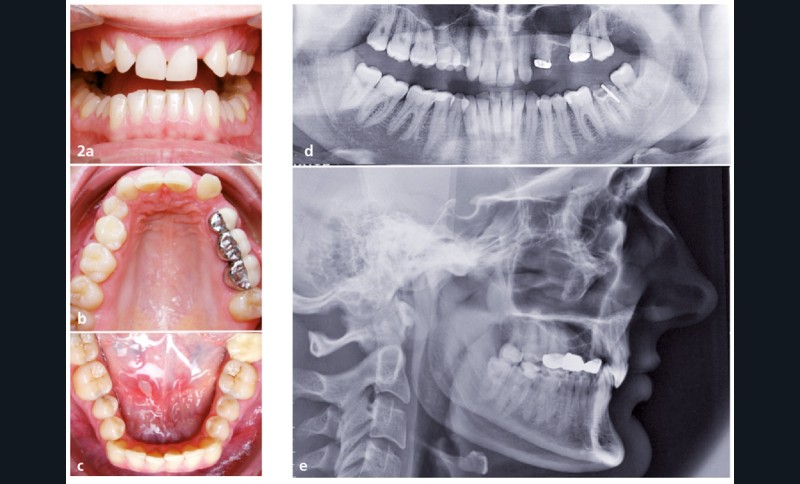

Les diagnostics sont très uniformes : classe II 2, schéma squelettique hypodivergent, bilan dentaire incomplet, quatre agénésies 1512 22 25 ; certains complètent avec l’asymétrie dans le plan frontal ou mandibulaire.

À la question « avez-vous déjà traité un cas identique ? », seules trois réponses sont positives. Les praticiens ont accepté de nous transmettre ces cas, mais nous n’en avons reçu que deux (le troisième est celui d’un jeune praticien qui ne l’a pas terminé). L’un des deux cas reçus est une classe III squelettique traitée sans chirurgie orthognatique et l’autre un cas de classe II 2 sévère sur un schéma squelettique classe II sévère. Dans les deux cas reçus, pas d’agénésie ni de…